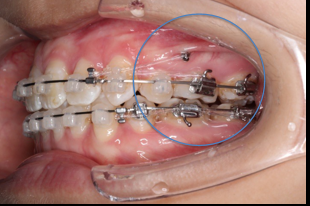

长时间使用TPA或者使用颌内支抗关间隙,容易造成第一磨牙和第二磨牙颚侧尖出现台阶,容易造成术后早接触及咬合关系不良

(引用其他病例图片)

上后牙:高度保持不变/压入性移动,尽量避免伸长;▲垂直向控制中,应防止上后牙颊侧倾斜(TPA);▲腭尖高度控制也重要。